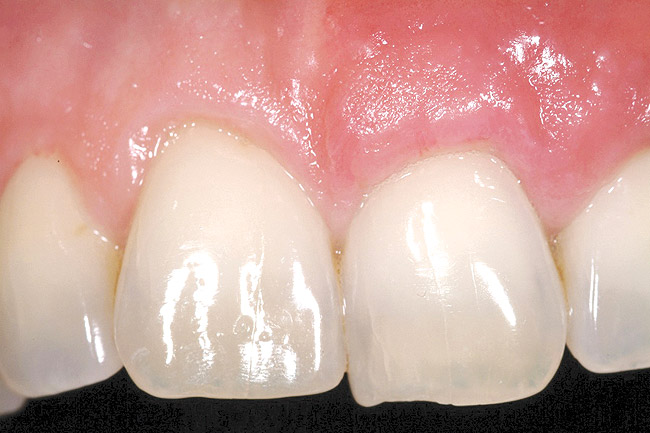

Figure 1  Case One Pretreatment clinical view, Case 1, maxillary right.

Figure 1

A 54-year-old non-smoking woman presented for correction of deep-wide gingival recession in the maxillary anterior (Figure 1 through Figure 3). The patient’s desires were to correct the gingival recession, balance the heights of contour of the tissues, and possibly undergo esthetic enhancement of the maxillary anterior with veneer restorations.

The 2-month postoperative view can be seen in Figure 13 through 15. Note the color match of the tissue, balance of the facial heights of contour, and zones of attached keratinized tissue present.